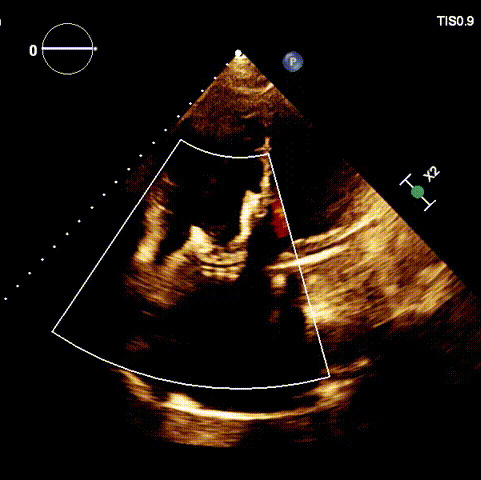

術后DSA

術后超聲